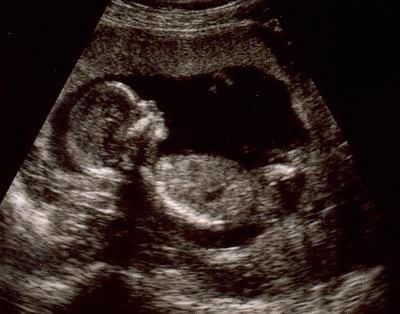

W zależności od twojego stanu i samopoczucia mogą być przepisane ogólne testy i ultradźwięki. Podczas skanowania lekarz sprawdzi ilość płynu owodniowego, pozycję łożyska. Ponadto główne wskaźniki płodu (rozmiary prywatne i ogólne, tętno itp.). Jeśli nadal znasz płeć swojego dziecka, dzięki udanej lokalizacji dziecka, specjalista będzie mógł ujawnić ci ten sekret.